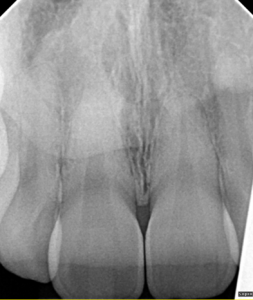

Clinical Cases